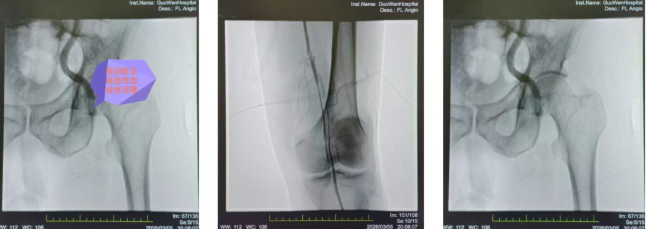

*患者左下肢血管造影图像

面对这一紧急情况,长春国文医院立即启动急诊绿色通道。血管外科团队迅速集结,在导管室连夜实施急诊介入手术。术中,团队争分夺秒、规范有序,精准开通闭塞血管,成功恢复下肢血供。

术后患者左下肢皮肤温度及感觉已基本恢复正常,生命体征平稳。从濒临坏死到转危为安,仅仅一夜之间,患者及家属对医院的快速响应和专业救治表达了由衷感谢。